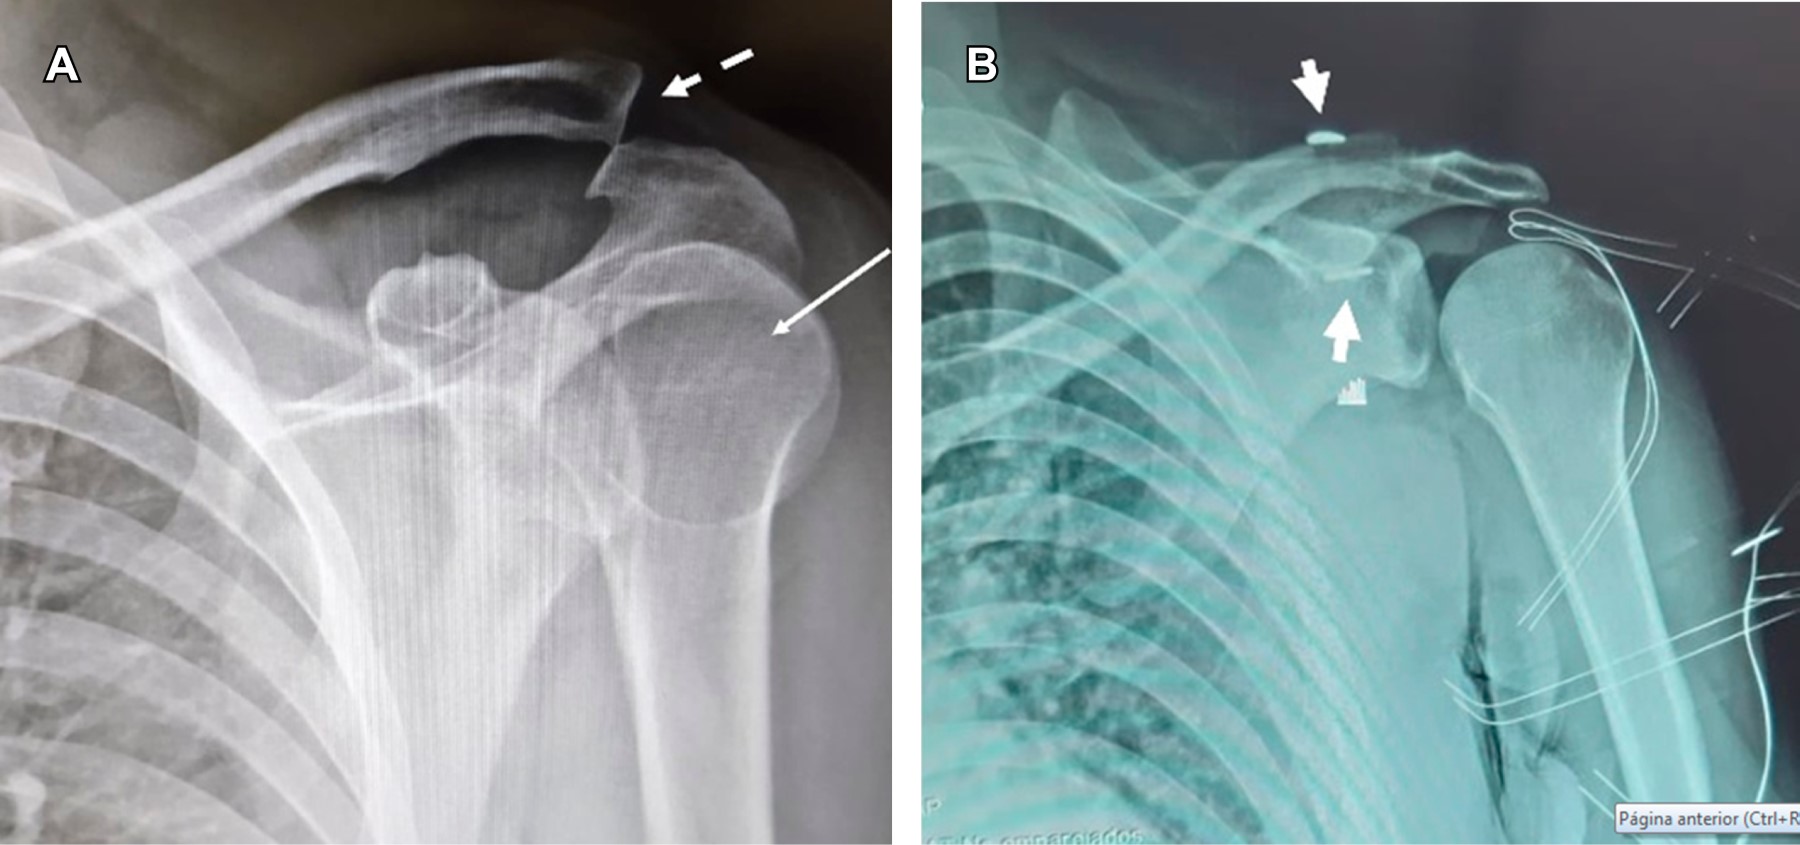

Posterior glenohumeral dislocation associated with grade III acromioclavicular dislocation

Figure 1